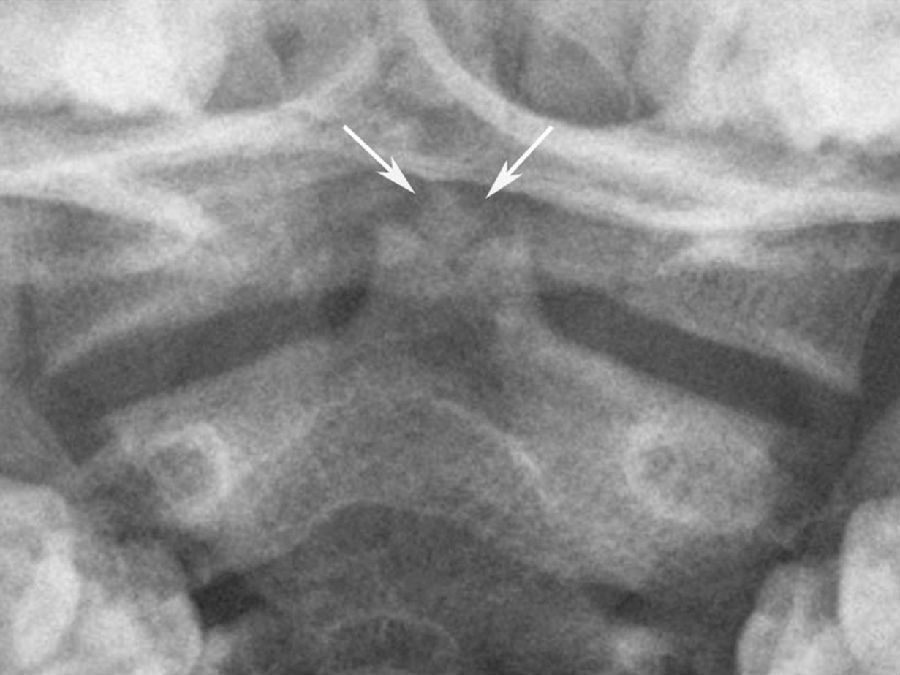

出生时,枢椎椎弓已有两个对称性骨化中心,4岁时融合。齿突骨化中心成对,脊索从其中部穿过。3~7岁时,齿突与椎体骨化中心融合,此时两个骨化中心之间仍有已退化的脊索和水平状的软骨联合存在。相互融合后,在此区域仍可残留骨硬化边、切迹或部分性裂隙,不能误认为是齿突骨折(图3)。齿突尖部单独骨化中心,可在出生时出现,但通常在第2年出现。齿突尖部骨化中心又称前寰椎或终末小骨,偶可孤立存在,但通常在12岁时与齿突骨化中心融合(图4)。终末小骨通常位于齿突尖部“V”形裂隙内,构成齿突尖部。

图4 齿突终末小骨

终末小骨(箭)位于齿突尖部“V”形裂隙内

齿突尖通常呈半球形,亦可为圆锥形,或呈逐渐变细的尖头状。齿突本身可呈尖爪形或球形,或明显细长超出寰椎前弓。齿突尖内偶可见局限性密度增高区,为终末小骨融于齿突所致。先天性齿突不连表现为齿突尖端和其下部分离,类似于骨折,两者区别在于先天性齿突不连无明显创伤史,且分离处有光滑的硬化边。枢椎上关节面内侧可见不同程度的裂隙状切迹,偶可呈孔状,为齿突和枢椎椎体骨化中心与先前的软骨区融合后的痕迹(图3)。齿突与枢椎体间的软骨盘可存留至成年,常有硬化边或椎体前面切迹(图3)。